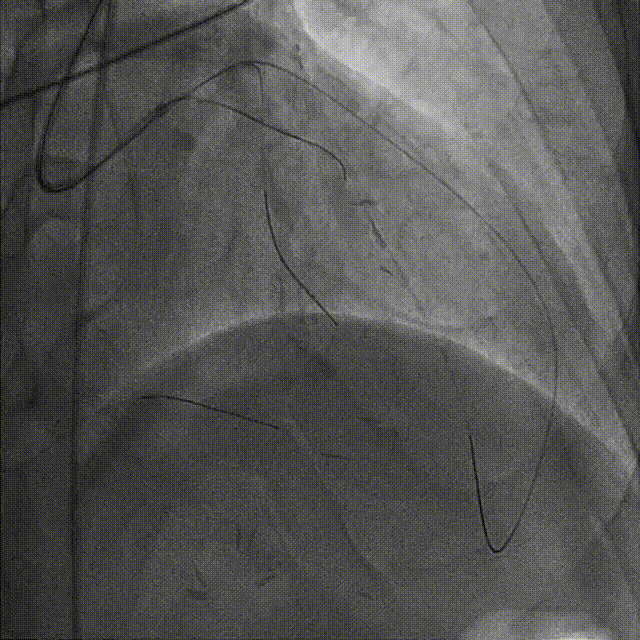

依次用Pinoeer 2.0mm x 15mm、Pinoeer 2.5mm x 15mm球囊至病变处反复扩张,送入Marvel导丝至D1远段做保护,LAD行IVUS检查。

IVUS检查示:可见导丝全程走行与血管真腔,近中段重度纤维增生斑块伴局部钙化,远段血管床废用性萎缩。

于LAD病变处由远及近依次植入XIENCE Alpine 2.5mm x 18mm和XIENCE Alpine 3.0mm x 23mm支架各一枚。